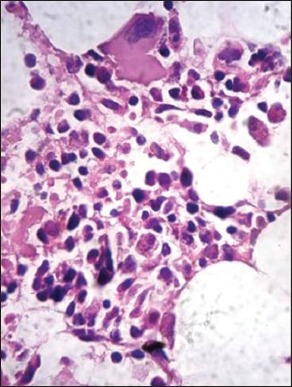

The clinicopathologic characteristics of all 14 patients with MM (13 newly diagnosed, 1 relapsed) are presented in Table 1. There were 11 males and 3 females with age range of 38-81 years (mean = 54 years, standard deviation = 10.7); and all were symptomatic at the time of evaluation. Eight (57%) were in Durie and Salmon Stage II, 5 (37%) Stage III and 1 (7%) in Stage I. Out of 14 cases, 10 (71.5%) presented with advanced lytic bone lesions, and two had organomegaly (one of which was de novo plasma cell leukemia). All, except one, had demonstrable light chain restriction (7 ‘ĸ’, 6 ‘λ’) by either IHC or biochemical assay techniques. Corrected serum calcium was found to be within normal range (≤11 mg/dL) in the majority of patients. On bone marrow evaluation, 10/14 (71%) cases showed an interstitial pattern of infiltration with or without focal nodularity; and 4 (29%) had packed marrow (diffuse pattern). Out of 14 cases, 10 (71%) cases were in Bartl's histologic Stage III (>50% tumor cells); and in 7 (50%), myeloma cells exhibited a high grade (blastic or pleomorphic) phenotype. Intracytoplasmic (Russell bodies) and intranuclear (Dutcher bodies) were noted in 11/13 patients; and in two intracytoplasmic crystalline inclusions were seen [Figures [Figures1a1a–g].

| Fig. 1c Bone marrow aspirate smears from patients with myeloma showing pleomorphic myeloma cells/plasmablasts (grade III). These cells are characterized by high nuclear to cytoplasmic ratio, polylobated nuclei with prominent nucleoli (Wright-Giemsa, ×400)